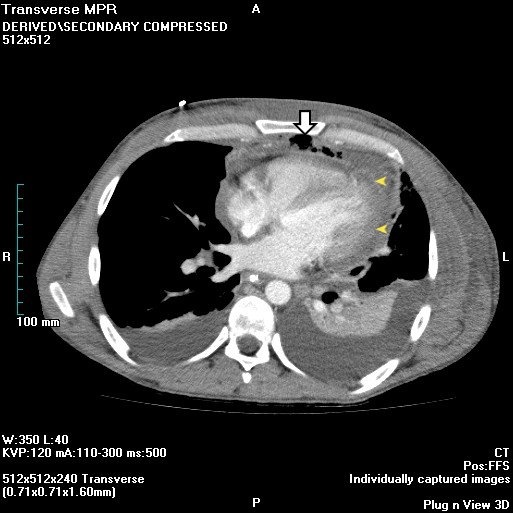

This patient presents with findings consistent with likely acute mediastinitis, a possible complication of cardiac surgery that is usually due to intraoperative wound contamination. Mediastinitis can complicate up to 5% of sternotomies. Patients typically present post-operatively (usually within 14 days) with fever, tachycardia, chest pain, leukocytosis, and sternal wound drainage or purulent discharge (as in this patient). Hamman’s sign is a crunching sound heard with a stethoscope over the precordium during systole and is suggestive of acute mediastinitis.

Chest x-ray usually shows a widened mediastinum in non-postoperative mediastinitis, but this can also be seen in postoperative mediastinitis after cardiac surgery. Chest radiograph findings include pneumomediastinum and/or air-fluid levels within the mediastinum. A CT scan can also support the diagnosis by demonstrating dehiscence of the sternum and stranding, fluid and air pockets within the anterior mediastinum. The diagnosis is usually clinically made and confirmed during surgery when pus is noted in the mediastinum. Postoperative mediastinitis requires drainage, surgical debridement with immediate closure, and prolonged antibiotic therapy. Antibiotics alone do not appropriately treat mediastinitis. Acute mediastinitis has a mortality rate of 10%–50%, even with appropriate treatment.